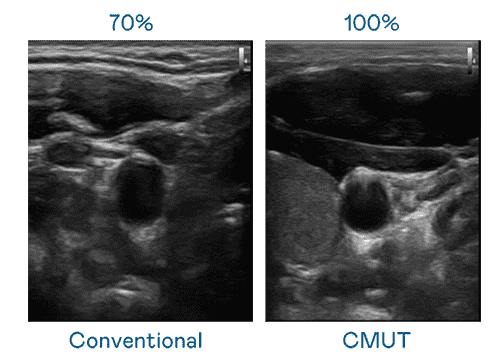

CMUT 技术是一种用电容式微机电元件来产生超音波讯号的技术。。与传统 PZT 压电式技术相比,,,,CMUT 频宽增加 30%,,更宽频的超音波讯号让影像解析度大幅提升,,,,是实现高影像品质医疗超音波扫描、、促进精准医疗发展的关键技术。。

大频宽带来超清晰影像

超音波影像的解析度高低,,首先取决于探头能发出的讯号频宽。。OBPay CMUT 可提供高清晰的超音波讯号,,提供高频宽、、高灵敏度、、、影像纹理细节更高的超音波影像,,协助医护人员缩短影像判读时间及利用精准的医疗影像进行诊断。。。